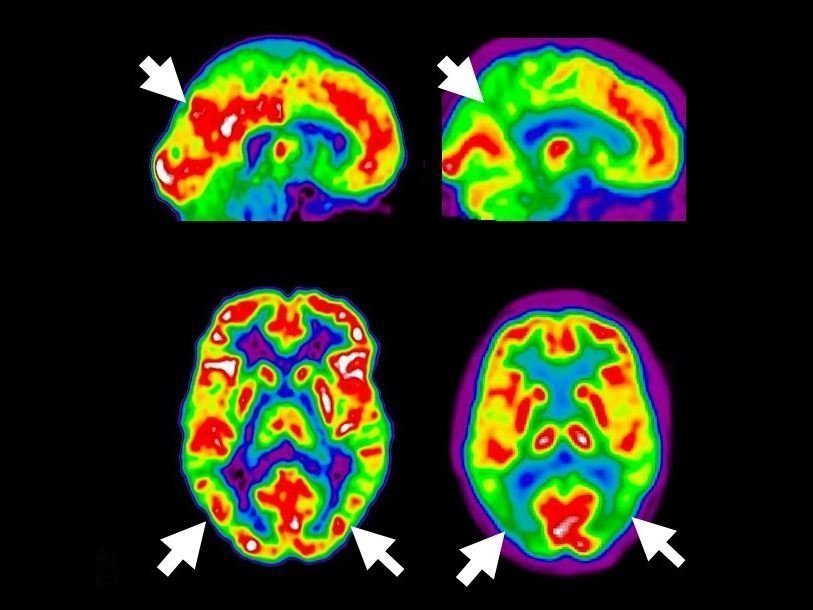

Томограмма мозга здорового человека и пациента с болезнью Альцгеймера Institut Douglas/Flickr.com Новое лекарство для борьбы с болезнью Альцгеймера предложила группа ученых из Йельского университета. Результаты их исследования опубликованы в журнале PLOS Biology.